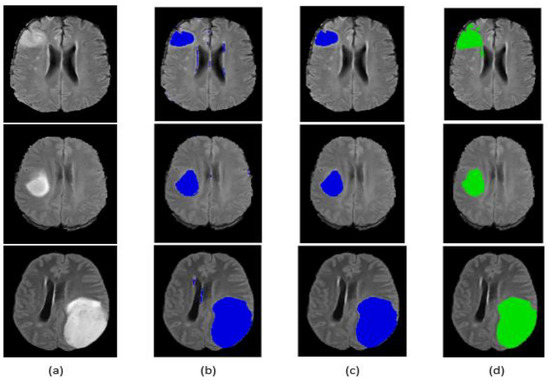

Qualitative segmentation results are presented in Figure 9 and Figure 10 for the BraTS 2017 dataset. The figures also indicate that our network is capable of accurately segmenting complete tumor regions. Our approach was tested on the FLAIR modalities for MRI images outside the BraTS 2017 dataset, and it provided good results, which guarantees the performance and power of the proposed method.

Figure 9.

Segmentation result of our method on some BraTS 2017 HGG images: (a) original image, (b) segmentation before post-processing, (c) segmentation after post-processing, (d) ground truth.